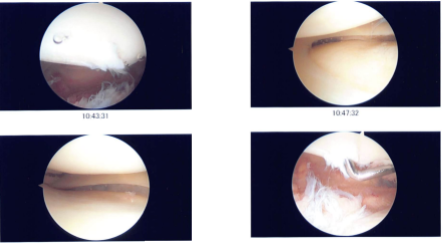

Preoperative antibiotic was given. A lateral entry portal was made and an arthroscope was inserted. Examination showed grade 2 to grade 3 osteochondral lesions over the posterior surface of the patella. A medial entry portal was made with the use of a spinal needle.

Examination of the medial tibiofemoral compartment showed intact medial meniscus and cartilage. Examination of the intercondylar notch showed intact ACL and PCL.

Examination of the lateral tibiofemoral compartment showed intact cartilage, but there was fraying of the anterior horn of the lateral meniscus, which was debrided with the use of a shaver to perform a lateral meniscectomy.

A shaver was also used to debride the posterior surface of the patella. Final pictures were taken and saved. The knee was thoroughly irrigated and drained. Closure was done with 3-0 nylon.

Intraoperative photo